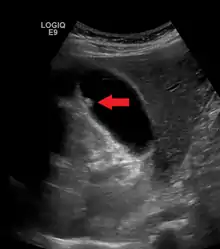

Gallbladder polyp

A polyp in the gall bladder as seen on ultrasound

Diagnosis is typically by ultrasound or CT imaging.